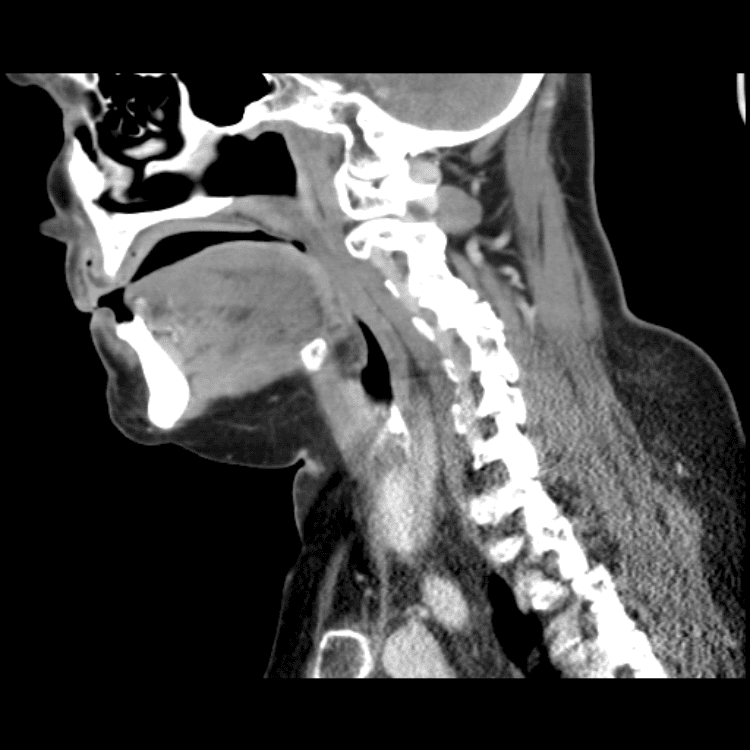

Head and Neck

Practice

Simulates call by including subtle or difficult cases and some normals.

27 cases